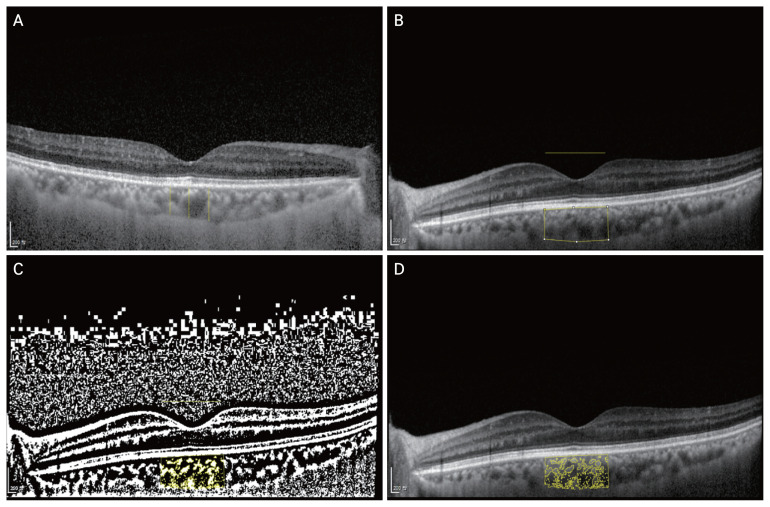

Methods: A total of 261 patients diagnosed with type 2 diabetes who had taken oral pioglitazone for more than 6 months were included in the study. After excluding patients who did not undergo regular eye examinations or who had ophthalmic surgery/interventions during the treatment period, a total of 40 eyes were included. The study examined the duration and dosage of pioglitazone, patient age, ocular axial length, refraction, glycated hemoglobin, systolic blood pressure, corrected visual acuity, macular thickness, choroidal thickness, and choroidal vascular index. Patients were categorized into a high-dose group if their pioglitazone dose was 30 mg or more per day, and a low-dose group if it was 15 mg or less. Choroidal thickness was measured below the subfovea and a 500 µm radius nasal and temporal to that location.

Results: Choroidal thickness significantly increased after 6 and 12 months of pioglitazone (6.70 and 13.65 µm, respectively) in all subjects. When stratified by pioglitazone dosage, choroidal thickness increased at 6 and 12 months in both high-dose group (4.48 and 0.84 µm, respectively) and low-dose groups (6.85 and 21.45 µm, respectively), with a greater change observed in the low-dose group (p < 0.05). Based on the location of choroidal thickness measurements, a significant increase in choroidal thickness was observed at 6 and 12 months of pioglitazone treatment in the subfoveal (7.00 and 13.15 µm, respectively) and nasal regions (6.43 and 19.24 µm, respectively), while a significant increase was only observed after 6 months of treatment in the temporal region (8.53 µm, p < 0.05). The largest increase in choroidal thickness was observed in the nasal side.

Conclusions: This study found that choroidal thickness increased in diabetic patients after taking pioglitazone. Regular eye examinations are recommended for diabetic patients who are on pioglitazone.